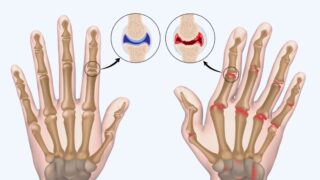

膝関節症、正式には変形性膝関節症と呼ばれるこの疾患は、膝の軟骨がすり減ることで痛みや腫れ、動きにくさを引き起こします。主に加齢や肥満、過度な負荷が原因で、40代以降の女性に特に多く、日本では約1,600万人が悩んでいると言われています。初期症状は階段の上り下りでの違和感ですが、進行すると歩行すら困難になります。治療法として運動療法や薬が一般的ですが、根本的な軟骨再生は難しいのが現状です。

軟骨の主成分はコラーゲンで、全体の約60%を占めます。加齢によりコラーゲンの生成が減少し、軟骨の弾力性が失われるため、関節が直接こすれ合うようになります。このメカニズムを理解することで、コラーゲンペプチドの役割がより明確になります。早期発見が重要で、痛みが続く場合は整形外科でのレントゲン検査をおすすめします。

コラーゲンペプチドは経口摂取後、血中を介して関節軟骨細胞に到達し、タイプIIコラーゲンの産生を促進します。これにより軟骨のクッション性が回復し、炎症性サイトカインの抑制も期待されます。動物実験では、CTP含有コラーゲンが軟骨の傷を通常より速く修復し、変形性膝関節症モデルの進行を遅らせました。

人間では、低分子量タイプ(LMCP)がKLグレードI/IIの患者で痛み軽減と機能向上をもたらします。これはコラーゲン分解酵素の活性低下と軟骨基質の保護によるものです。また、QOL(生活の質)向上もWOMACやVASスケールで測定され、日常動作の改善につながります。長期摂取で予防効果も見込まれます。